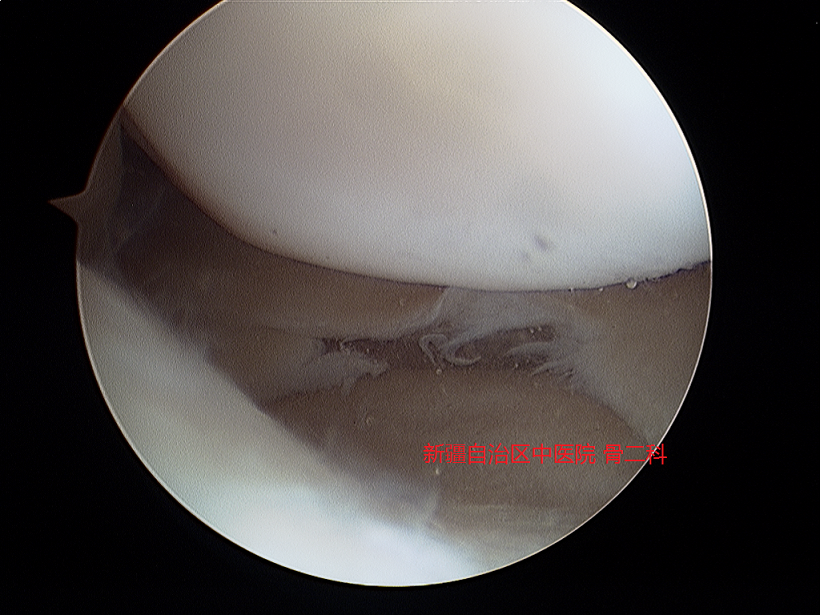

4.半月板损伤的微创手术处理

半月板损伤通常采用关节镜微创手术处理,分修整与缝合两种。

修整

缝合